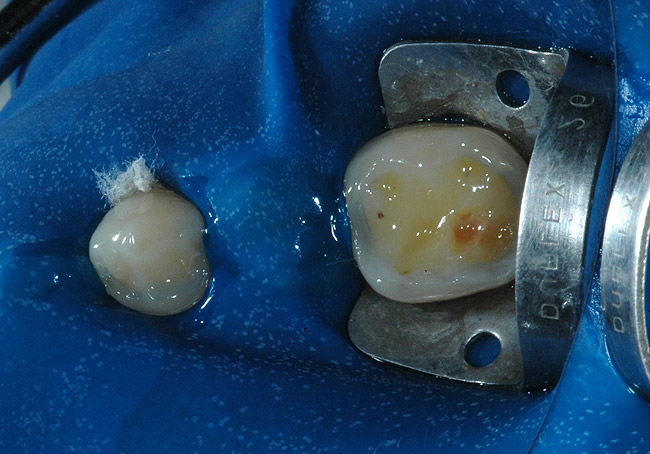

În cursul examinării clinice s-a notat o igienă orală satisfăcătoare. Pacientul prezenta coroziunea suprafeţelor ocluzale şi orale la dinţi maxilari şi mandibulari posteriori (fig. 1). Avea, de asemenea, arii expuse de ţesut dentinar (fig. 3) şi restaurări din amalgam compromise în lipsa sprijinului adecvat.

Aria posterioară a lingurii din acetat a fost secţionată în regiunea caninului şi a primului premolar şi piesele au fost utilizate pentru a restaura dinţii posteriori. S-au selectat culorile A2 pentru dentină şi A2E pentru smalţ. Cavităţile preparate pentru leziunile de coroziune au fost limitate prin îndepărtarea restaurărilor preexistente. S-a optat pentru izolarea absolută cu digă a câmpului de lucru, intercalând dinţii pentru a evita contactul compozitului cu suprafeţele aproximale. După profilaxia cu pulbere, suprafeţele de smalţ au fost gravate cu acid fosforic 37% timp de 30 secunde (fig. 5). După clătirea cu sprayul de apă/aer pentru 30 secunde, s-a aplicat un adeziv autogravant pe smalţ şi pe dentină şi s-a polimerizat cu lampa cu halogen la 500mW/cm2 timp de 20 secunde (fig. 6).